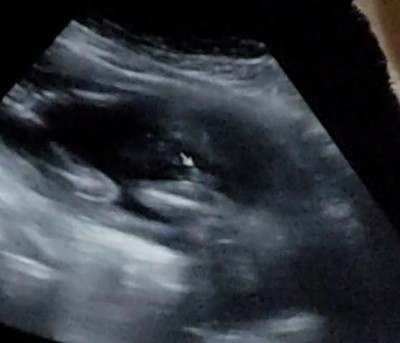

Doktor başta erkek sonra kız dedi ama cokda üstünde durmadı sizce nedir bacak arası ultrason fotoğraflı

Hiç anlamam. Kız diyorum

Erkek gibi hissettim

Kiz diyorm ben 3 cizgi